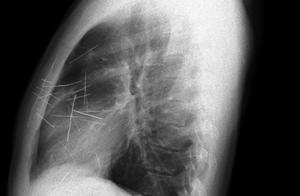

Classics inquiry, do not have food like that like that medical history of allergy history, eczema and medical history of familial member asthma, eliminated a bacterium to affect through the examination such as hematic convention, course lung CT and gas after three-dimensional rebuild show: As good as of double lung essence constant, bronchus of the leaf below right lung is initiative shadow of place density heighten, height suspects spirit way the eyewinker.

As expected, it is on the right side of the little patient advocate bronchus mouth place discovers half pignut.